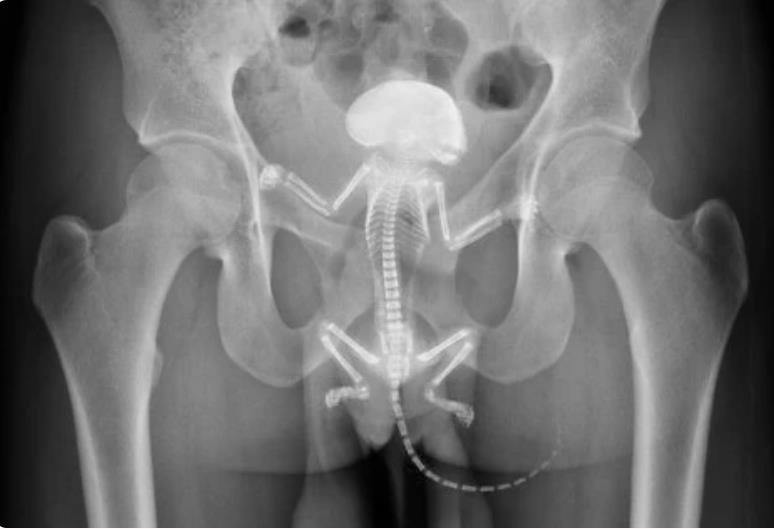

弗蘭克佛特被緊急送醫救治,外科醫師花了2小時手術將松鼠取出,弗蘭克佛特有嚴重的內出血,所幸術後情況穩定下來,然而可憐的松鼠沒度過此劫不幸死亡。